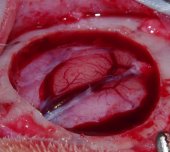

– Goyenvalle, 2012 (2) – Source : Rapport CORTECS – Rapport sur l’ostéopathie crânienne établi par le Collectif d’enseignement et de recherche en esprit critique et sciences (CORTECS), p.76-77 – Il s’agit d’un mémoire d’un étudiant en école vétérinaire – Si je me présente page 6 comme – un « jeune » étudiant en ostéopathie – trois paragraphes plus tard je précise que je suis Enseignant Chercheur en Chirurgie à ONIRIS, membre d’une équipe INSERM. – Il n’y a pas mention d’objectifs de recherche clairement défini ni de formulation d’hypothèses de recherche a priori. Ce qui s’apparente le plus à une présentation d’objectifs de recherche dans ce mémoire est ce passage, page 6: « Me voilà en tout cas, à cette date du 7 Mai 2009, avec une certitude : il existe bien un mouvement rythmique du cerveau; mais aussi beaucoup de questions qui persistent : – pourquoi autant d’aléa dans le délai d’apparition de ce mouvement après ouverture de la boite crânienne ? – pourquoi une telle impression de variabilité de ce mouvement entre différents animaux, tant sur le plan de la fréquence que de l’amplitude ? – Cette motilité cérébrale, est-elle synchrone d’autres mouvements physiologiques comme la respiration ou la fonction cardiaque ? – existe-t-il une relation entre la contraction/expansion cérébrale et les mouvements de flexion/extension du sacrum, comme le laisse penser le concept cranio-sacré de Sutherland ? » – En quoi cela ne correspond pas à des objectifs de recherche ? Je pose 4 questions auxquelles je vais essayer de répondre – Ce travail part donc du présupposé qu’il existe bel et bien un « mouvement rythmique du cerveau », sans pour autant renvoyer à une littérature spécifique – C’est une observation que j’ai faite de mes yeux et filmée avec un caméscope de marque SONY etc…, à l’occasion d’une intervention chirurgicale pratiquée le 7 Mai 2009, comme je le rapporte au 3ème paragraphe de la page 6, en donnant la référence internet montrant la vidéo : http://www.osteo4pattes.fr/films/vetosteo2wmv.mpg). Une méthodologie détaillée est ensuite présentée. Nous allons la présenter puis voir si elle permet de répondre aux potentiels objectifs de recherche formulés. – Sept lapines de race New Zealand, provenant d’un élevage, ont été anesthésiées, puis craniotomisées. Avant et après craniotomie, certains paramètres ont été mesurés durant 45 minutes sur chacune des lapines. Le protocole de relevé des mesures n’a pas été défini a priori ni standardisé. – Sur quelle base les auteurs peuvent dire que les paramètres de mesures n’ont pas été définis à priori, bien au contraire. Je précise p.7 « En tant qu’enseignant – chercheur en Chirurgie, j’ai la chance d’avoir accès à des infrastructures et moyens qui me permettent de réitérer les observations faites précédemment, et donc d’élaborer un protocole d’étude pour apporter des réponses à mes différentes interrogations concernant la pulsatilité cérébrale…. » J’ai donc rédigé mon protocole et ensuite réalisé l’étude, comme cela doit se faire pour toute étude. – Les paramètres mesurés ont été : la fréquence cardiaque, la fréquence respiratoire, la fréquence thoracique, la pulsatilité cérébrale (à travers sa fréquence (3) et son amplitude(4), la fréquence du cycle Inspir/Expir du sacrum (5), les restrictions de mobilité du sacrum(6). Nous avons ajouté une description de ces derniers paramètres en note de bas de page car ils sont spécifiques aux ostéopathes. Deux nouveaux éléments posent problème à ce stade : l’existence physique des paramètres étudiés ; la validité et la fiabilité des techniques utilisées pour les mesurer (Notre partie XXX porte d’ailleurs sur l’étude de la fiabilité des outils et techniques diagnostics ostéopathiques). Il n’est à a aucun moment mention de la façon dont la mesure de ces paramètres va permettre de répondre aux nombreuses questions de recherches soulevées initialement. – A noter que les deux paramètres qui posent problème de validité aux auteurs ne sont utiles que pour répondre à la 4ème et dernière question de la liste des objectifs rapportés précédemment. Pour les trois premières questions, les méthodes d’évaluation des paramètres mesurés ne peuvent pas être remises en question… Elles font d’ailleurs l’objet d’une analyse critique de la méthodologie dans la première partie de la discussion. Je rappelle juste à ce stade, que la partie Matériel et Méthodes est là pour décrire précisément la méthodologie utilisée. A l’exception des paramètres (5) et (6) uniquement accessibles aux ostéopathes, tout à chacun peut, sur la base du Matériel et Méthodes rapporté, reproduire l’étude à l’identique et ainsi faire ses propres observations. – La partie résultats du mémoire s’articule en deux temps : une synthèse par individu des paramètres observés ; une synthèse par paramètre. Cette partie ne permet en rien de répondre aux questions de recherches précédemment formulées. – Comme dans toute étude scientifique, la partie Résultat expose les résultats bruts sans aucune analyse. Cela rend la lecture de la partie Résultats fastidieuse, mais c’est ainsi selon les bonnes pratiques de rédaction scientifique. L’analyse des résultats est faite dans la partie Discussion. La partie discussion est constituée principalement (pp.37 à 49) de sous-parties intitulées respectivement. En toute objectivité, il conviendrait de préciser que le Matériel et Méthode fait l’objet d’une analyse critique (page32 à 35) : – la dure-mère : élément de tenségrité de l’axe cranio-sacré ; – la pulsatilité cérébrale existe ; – la pulsatilité cérébrale : un rythme propre ? – la pulsatilité cérébrale : moteur du MRP ? Dans ces sous-parties, il n’est à aucun moment fait mention des expériences menées précédemment. – Le terme « à aucun moment » révèle une lecture très incomplète du document. Pour exemple : * dans le paragraphe « Dure-mère : élément de tenségrité de l’axe cranio-sacré » , est écrit dans le 3ème paragraphe de la page 38 « Dans notre étude, à la suite de la craniotomie, le système de tenségrité de l’axe cranio-sacré s’est retrouvé modifié, en particulier la dure-mère (par son effraction), et par voie de conséquence le LCR (fuite de LCR à l’origine d’une baisse de volume et de pression) ….Lors d’effraction latéralisée, nous avons ressenti, en plus de la flexion, l’apparition d’une rotation du sacrum, avec une rotation toujours dans le même sens par rapport au côté de l’effraction. Ce qui fait que la main sur le sacrum, je pouvais annoncer au chirurgien de quel côté se produit l’effraction dure-mérienne. » – dans le paragraphe « la pulsatilité cérébrale existe», est écrit dans le 3ème paragraphe de la page 41 « Ces différentes observations rapportées dans l’ouvrage de Swedenborg concordent parfaitement avec les nôtres. A deux différences près : (1) – qu’il n’est jamais rapporté l’existence d’un délai dans l’apparition de la pulsatilité cérébrale par rapport au moment de la craniotomie. Il faut noter que toutes les observations rapportées à l’époque proviennent de patients (humains ou animaux) parfaitement vigiles – avec toute l’horreur que cela représente. Cela ne fait que renforcer notre conviction (émise précédemment) que l’anesthésique utilisé dans notre étude est à l’origine de l’apparition retardée de la pulsatilité cérébrale par rapport au moment de la craniotomie. (2)- Nos observations montrent que l’effraction dure-mérienne large est une condition nécessaire à l’observation visuelle d’un mouvement d’expansion / rétraction du tissu cérébral. Aucune pulsatilité cérébrale n’a été observé pour les lapins n°2 et 3, animaux pour lesquels l’intégrité de la dure-mère a été largement préservée. Pour tous les autres lapins (n°1, n°4, n°5, n°6 et n°7), dès lors que la brèche dure-mérienne est large, un mouvement d’expansion / rétraction du tissu cérébral apparaît après un certain laps de temps (en moyenne 45-50 minutes postinduction anesthésique). Seul Ridley précise dans son observation que la dure-mère a été ouverte. Pour les autres, rien n’est précisé….. Et ainsi de suite dans les différents paragraphes de la discussion des résultats. Je laisse le soin aux lecteurs de se faire sa propre opinion. – L’auteur cite des travaux ou hypothèses d’autres auteurs. Un tableau présenté dans son étude résume les résultats des expériences menées sur les lapines sans faire mention du MRP. – Cela montre que les membres du groupe CORTECS n’ont pas bien lu les objectifs de mon étude, qui n’ont rien à voir avec le MRP. – Cette étude ne nous apporte aucune preuve d’existence du MRP – Contrairement à ce que sous-entendent les rapporteurs du CORTECS, l’objectif de cette étude, comme le titre l’indique, n’est pas de prouver l’existence du MRP, mais d’en savoir un peu plus sur le rôle de la pulsatilité cérébrale dans le concept cranio-sacré tel que décrit par Sutherland. – elle pose au départ que ce phénomène existe – Il y a là de la part des auteurs du groupe CORTECS clairement confusion entre le MRP et pulsatilité cérébrale. Je pose au départ que la pulsatilité cérébrale existe, car j’ai personnellement observé ce phénomène, je l’ai d’ailleurs filmé. D’ailleurs tous les neurochirurgiens l’observent au quotidien, et qu’elle se contentera d’étudier certaines de ses caractéristiques. – La méthodologie déployée ne permet pas de répondre clairement aux questions de recherche formulées – Comment peut on oser dire que le comptage visuel des mouvements cérébraux n’est pas fiable ? Comment oser dire que le comptage visuel des mouvements thoraciques couplé à un comptage par un capnomètre n’est pas fiable pour mesurer la fréquence des mouvements respiratoires ? Comment peut-on oser dire que l’utilisation d’un ECG n’est pas fiable pour mesurer la fréquence cardiaque ? – Qui ne sont pas reprises dans la partie résultat ou discussion – Comment peut-on oser dire que les questions ne sont pas reprises dans la discussion, eu égard à mes remarques précédentes? – Les principales limites de cette étude sont : – l’absence de présentation claire des objectifs visés par l’étude, et l’absence d’identification des critères de jugements permettant de répondre aux questions de recherche imprécises ; – la validité et la fiabilité des outils utilisés pour mesurer les paramètres ; – l’existence physique de certains des paramètres étudiée : existent-ils réellement ? – Dans son concept cranio-sacré, Sutherland considérait la mobilité inhérente du cerveau (que j’ai appelé la pulsatilité cérébrale) comme le moteur du MRP. L’une des conclusions de mon étude (dernier paragraphe p.48) est que « … à la question posée « Pulsatilité cérébrale : moteur du MRP ? », ma réponse actuelle serait non… ». Ma conclusion remet donc en question le concept cranio-sacré, telle que décrit par Sutherland. Cela peut paraître surprenant de la part d’un vétérinaire ostéopathe, mais l’honnêteté scientifique conduit parfois à remettre en cause certaines idées. Loin de moi l’idée de vouloir prouver que le MRP existe sur la base de résultats sans valeurs scientifiques, comme le laisse sous-entendre les auteurs du Cortecs. Mais peut-être que les auteurs du CORTECS font une allergie systématique à tout document parlant du MRP….. Je laisse maintenant le soin aux lecteurs de se faire sa propre opinion sur mon étude et sur l’analyse qui en a été faite par le Cortecs. Notes 2 Goyenvalle E., La pulsatilité cérébrale dans le concept cranio-sacré – Étude chez le Lapin, Mémoire en vue de l’obtention du diplôme d’ostéopathie vétérinaire d’ON×Î×S – École Nationale Vétérinaire de Nantes 2012, revue ostéo4pattes. https://revue.osteo4pattes.fr/IMG/pdf/Memoire_Osteopathie_26-06-12_goyenvalle.pdf 3 « À travers l’ouverture de la boite crânienne, le cerveau a montré des mouvements rythmiques d’expansion/contraction, se traduisant par une montée / descente de la surface cérébrale par rapport à la marge osseuse du défaut osseux de craniotomie. La fréquence de ces cycles montée/descente a été comptabilisée par minute. ». Ibid. 4 «Elle a été classée en trois groupes : faible (mouvement limite perceptible), moyenne (mouvement perceptible sans dépasser les limites des marges de craniotomie), élevée (mouvement perceptible qui dépasse les marges de la craniotomie) ». Ibid. 5 « La main gauche est posée sur le sacrum à l’écoute du mouvement d’inspir/expir (Extension/Flexion) de ce dernier. La fréquence des cycles Inspir / Expir a été comptabilisée par minute ». Ibid. 6 « La main posée sur le sacrum évalue les restrictions de mobilité pouvant être observée (flexion, extension, rotation, side-bending) ». Ibid.NDLR : Ces quelques lignes montrent que quelles que soient la motivation et la bonne volonté des auteurs de ce rapport, de nombreuses imprécisions ou incompréhensions ou élusions ont été commises. Quoi de plus normal quand on passe en revue des dizaines d’études et c’est bien là la limite de l’exercice qu’ils ont accompli, et qui montrent que d’études en études le petit parti pris plus ou moins conscient du départ s’installe et donne une conclusion sinon partiale en tous cas qui ne trie pas correctement le bon grain de l’ivraie … Effectivement Eric nous a très bien parlé de pulsatilité cérébrale observée sous plusieurs angles … ce n’est pas un présupposé de sa part, comme affirmé par les auteurs du Cortecs, c’est une observation … qualificatif assez péjoratif quand infondé quand on commence l’étude d’une étude et qui laisse penser que sa propre étude est entachée de présupposés. L’arroseur arrosé ! Autre malentendu rapporté ces lapins n’ont pas été sacrifiés sur l’autel de la probation le la pulsatilité cérébrale mais cette expérimentation s’appuyait sur la première expérience pour laquelle ces lapins étaient opérés : la biocompatibilité de matériaux pour restaurer une boite crânienne abimée (par un accident de la route ou un éclat d’obus …). Aucune souffrance supplémentaire n’a été infligée pour les besoins de cette deuxième expérience pendant l’expérience. J’aimerais actualiser ma petite touche personnelle car ce sujet, bien que datant maintenant d’une dizaine d’année est brûlant d’actualités. Des experts (autoproclamés il faut le dire) prennent un sujet, regarde les études réalisées sur le sujet et concluent sur la validité scientifique de ce qui a été produit. Cela s’appelle une méta étude et c’est en ce moment le nec plus ultra de la science. Mais comme pour tout, le diable se niche dans les détails. Et sur cette étude particulière, ils sont pris en flagrant délit de lecture en diagonale et de parti pris. Qu’en est ‘il alors pour les autres études du rapport ? Et l’on voudrait que ces gens-là nous expliquent « ce qui est » et doit être à l’exclusion de tout autre ? Vous trouverez dans ces articles sur les cadres de pensée entre autres comment une telle méta étude a « démontré » avec gracieuse mauvaise foi que l’homéopathie ne valait rien : http://osteo4pattes-sdo.eu/spip.php?article2959. Or, ici, Eric nous montre (pour nos yeux) que la pulsatilité du cerveau existe et est quelque chose d’incontournable. De plus, Eric nous dit aussi qu’il ne sait pas après son étude si le MRP et la pulsatilité observées sont liés. Vous savez sans doute que je pense que pour expliquer ce que nous sentons dans nos mains il faut passer par la résonance d’un système de tenségrité. Ai-je tort ou raison scientifiquement ? Je n’en sais rien. Mais je sais deux choses : 1) C’est que l’explication de Sutherland n’est peut-être pas la bonne, tant elle piétine à fournir des preuves de son existence. 2) Je sais aussi que nous sentons vraiment quelque chose dans nos mains que nous nommons MRP et que ce concept produit des effets. Alors, Il faudra bien effectivement un jour que science et expérience se rejoignent. Mais je suis aussi persuadé que pour cela il faudra que la science médicale élargisse sa conception de la vie …